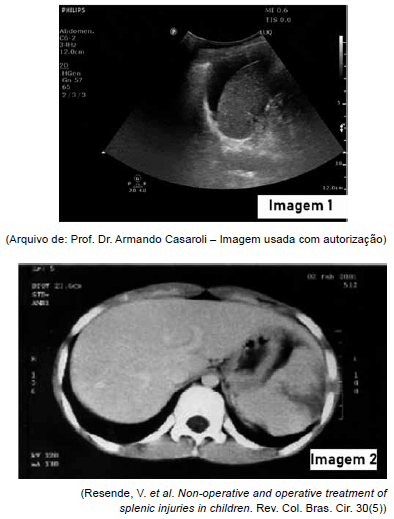

Homem de 25 anos sofre agressões no abdome e dá entrada na emergência consciente, referindo dor abdominal. Realizada avaliação e atendimento iniciais a contento, apresentando estabilização hemodinâmica. Com relação ao achado do e-FAST, demonstrado na imagem 1 (demais focos sem alterações), e a tomografia computadorizada de abdome (imagem 2), pode-se concluir, corretamente, que o paciente apresenta: